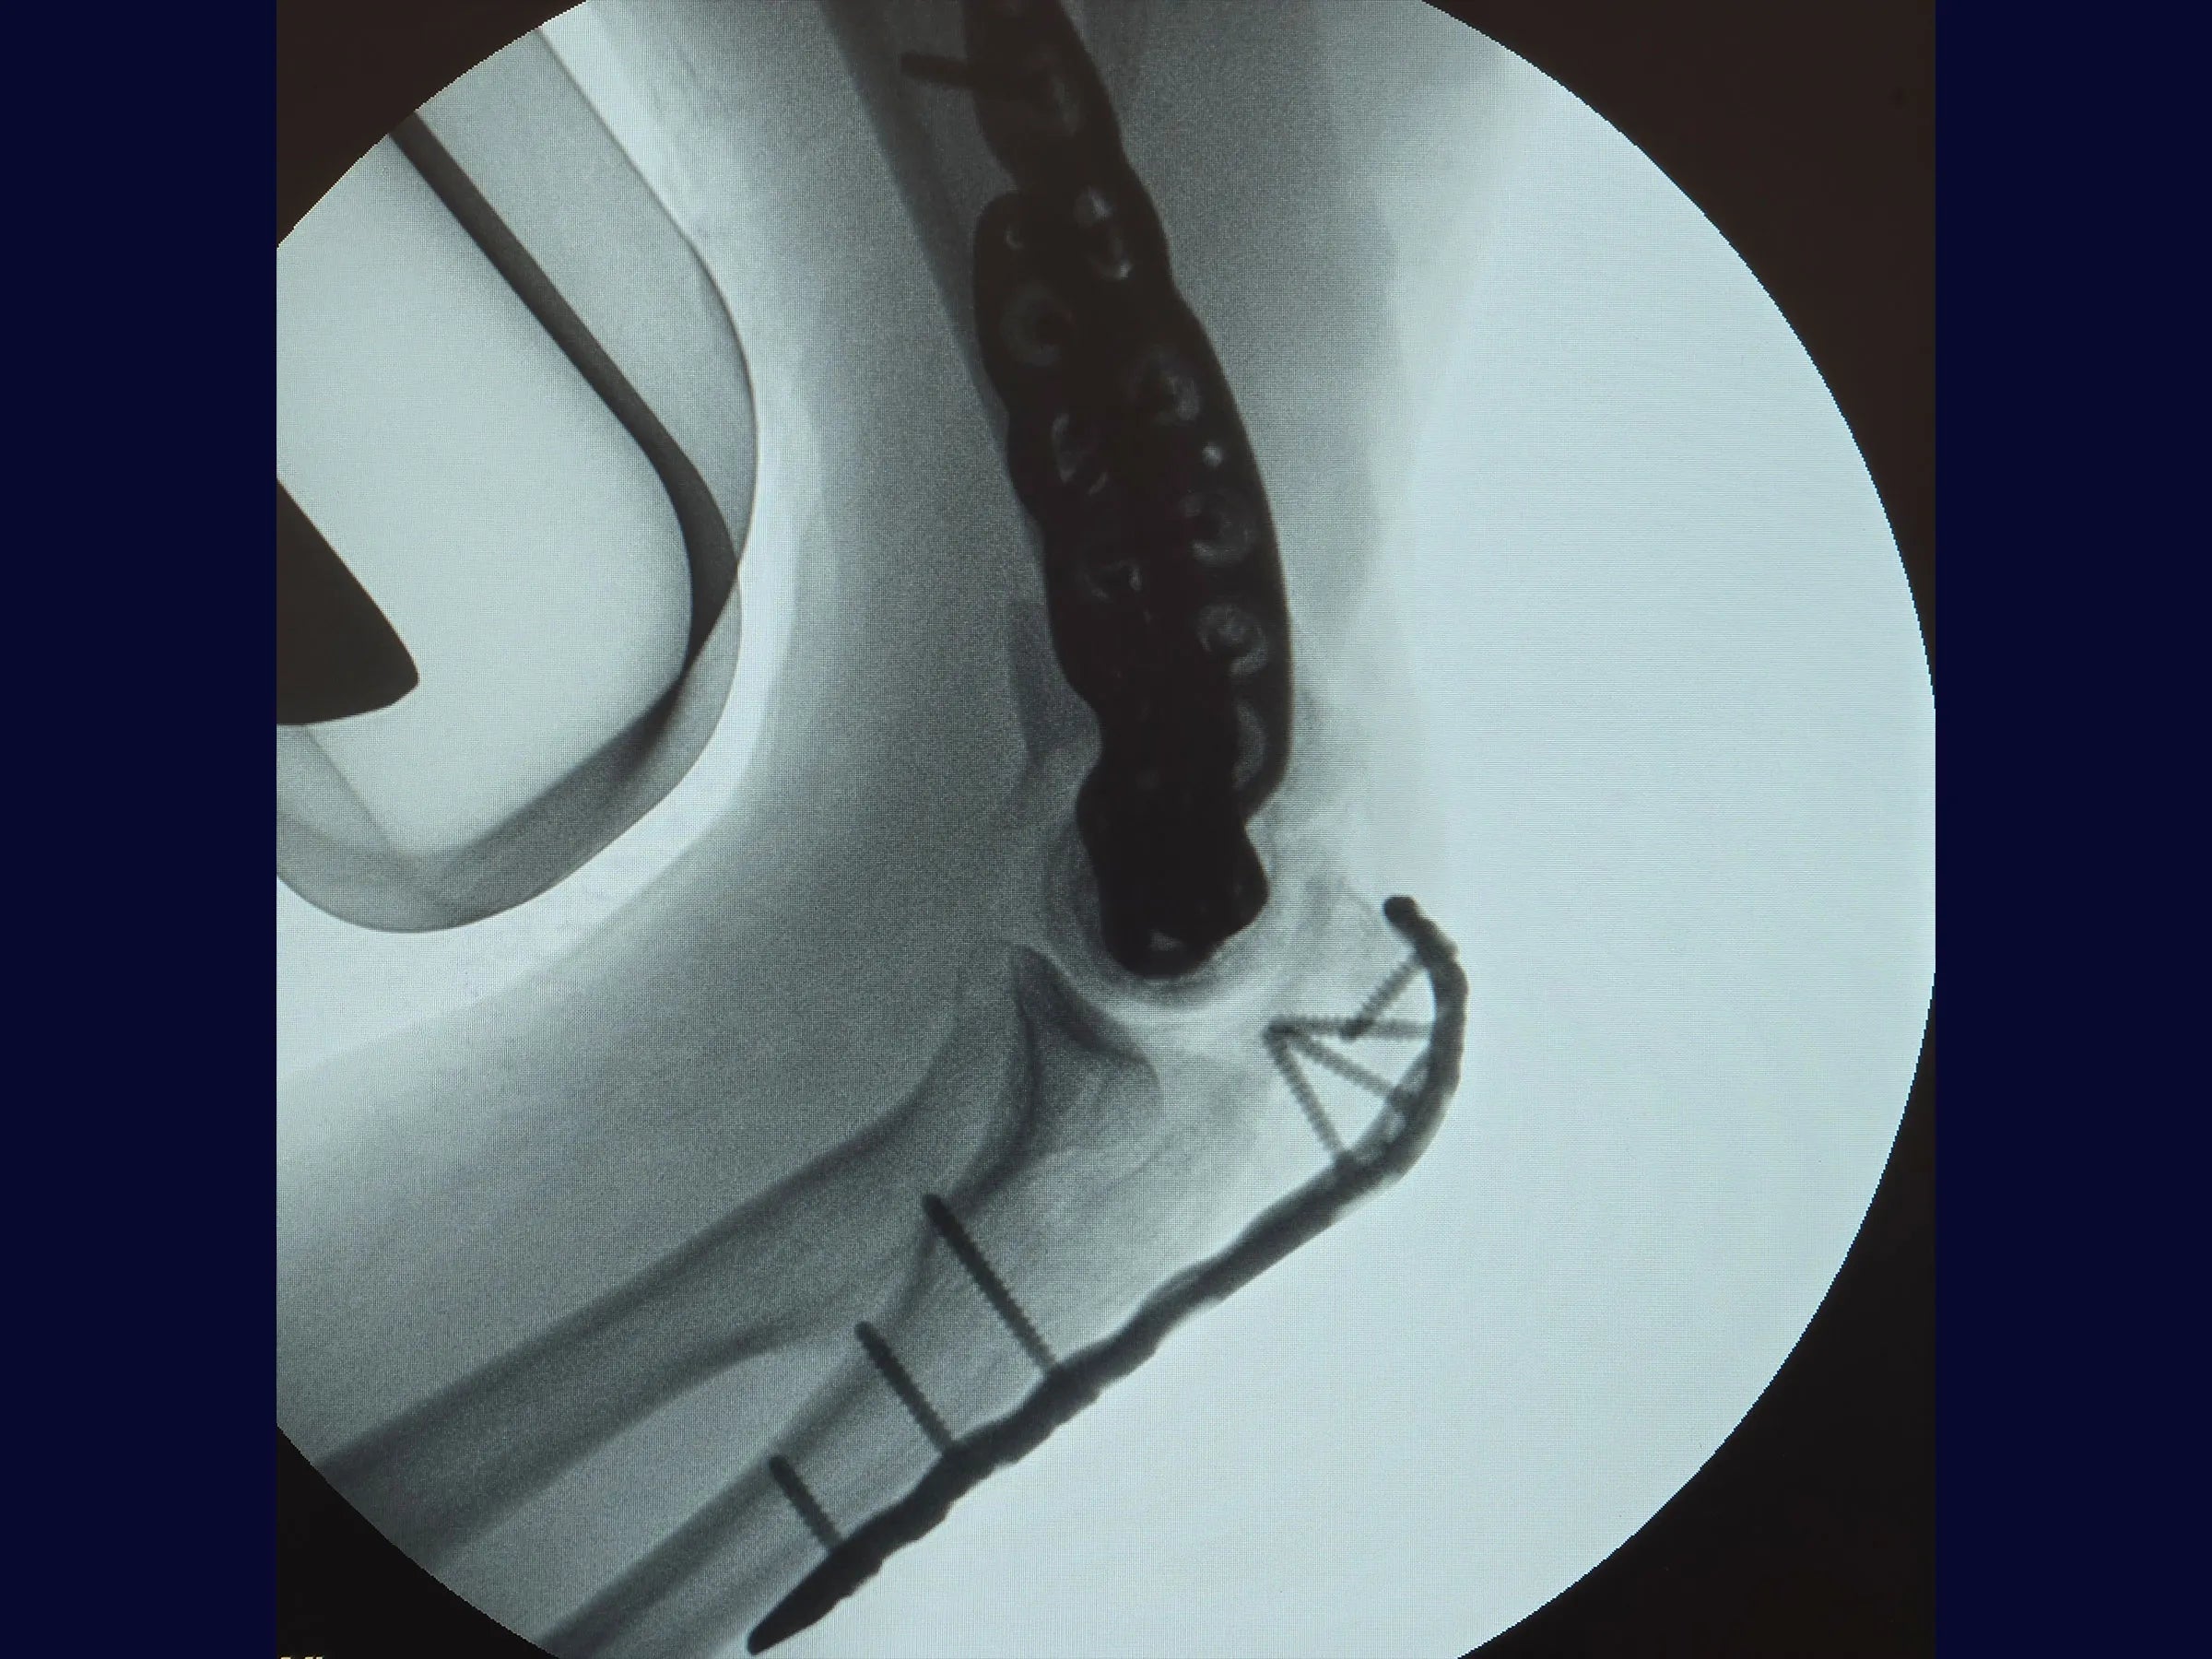

- Osteotomia em Chevron no olécrano para ampla exposição articular.

- Fixação definitiva com placas bloqueadas de ângulo variável.

- Osteotomia Precisa: Chevron no olécrano com preservação da cartilagem, garantindo estabilidade e preservação anatômica na reconstrução.

- Fixação Estável: Aplicação de placas bloqueadas de ângulo variável para alinhamento seguro e resistência biomecânica.